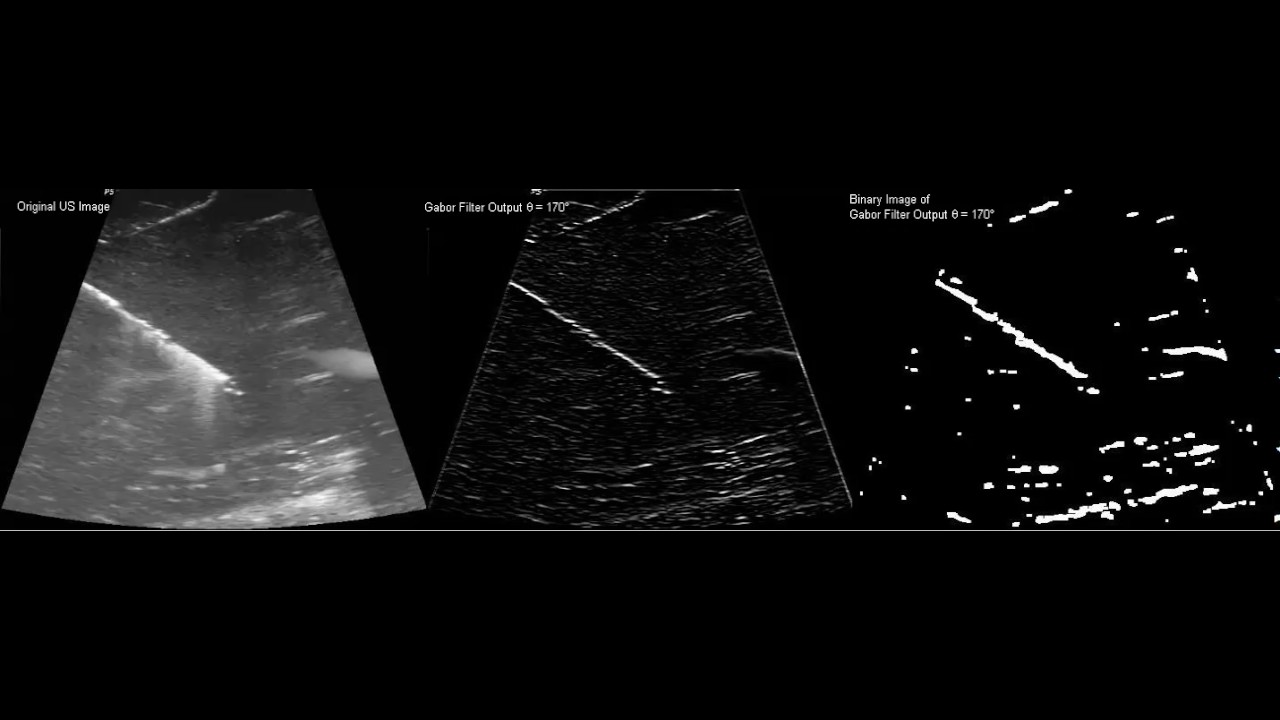

Visual tracking of biopsy needles in 2D ultrasound images

Mert Kaya; Enes Senel; Awais Ahmad; Ozkan Bebek

2016 IEEE International Conference on Robotics and Automation

DOI: 10.1109/ICRA.2016.7487637